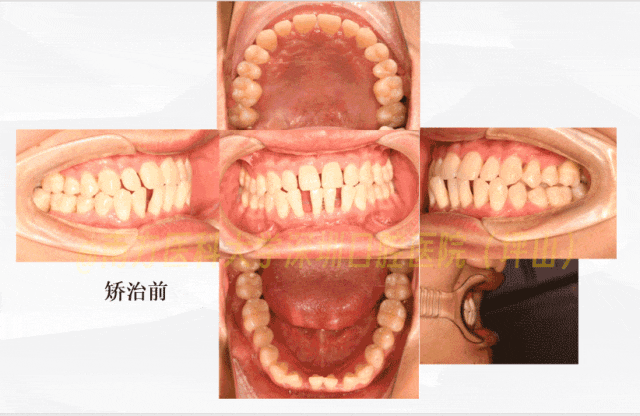

矫治过程回顾

矫治前